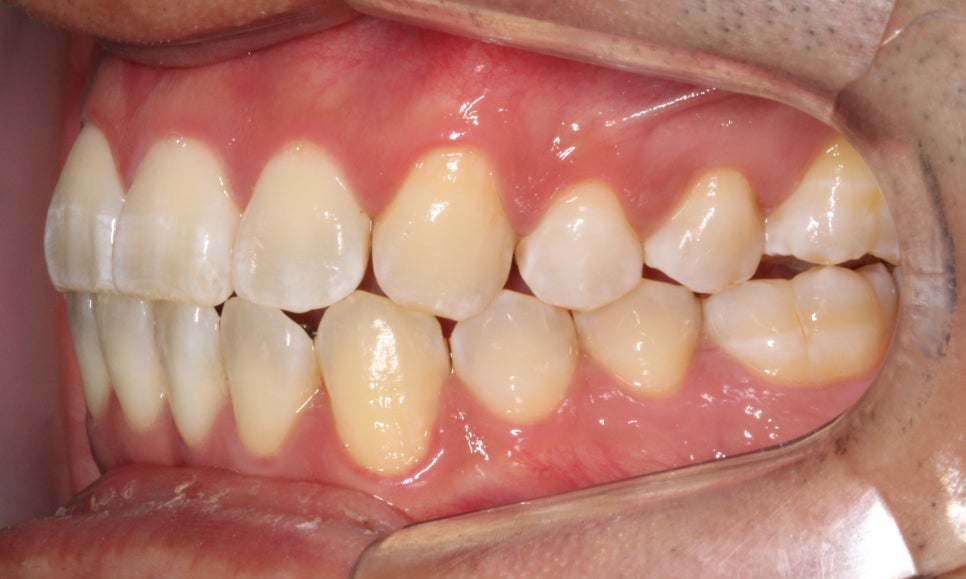

부분교정을 진행을 할 때에는

송곳니 위치와 구치부 교합관계를

꼭!!! 평가를 하는데요.

앞서 말씀드린 것처럼

송곳니 위치의 문제라기 보다

그 옆 치아가 상대적으로 들어가 있어서

덧니가 심해 보이는 모습이라,

제 기준으로는

충분히 부분교정이 가능해 보였습니다.

아래 앞니도 공간이 부족해서

약간 삐뚤빼뚤한 모습이 나타나지만

충분히 비발치 부분교정으로

펼칠 수 있는 케이스라 판단했습니다.

안 보이는 장치를 희망하셔서

2D교정으로 진행하기로 했습니다.